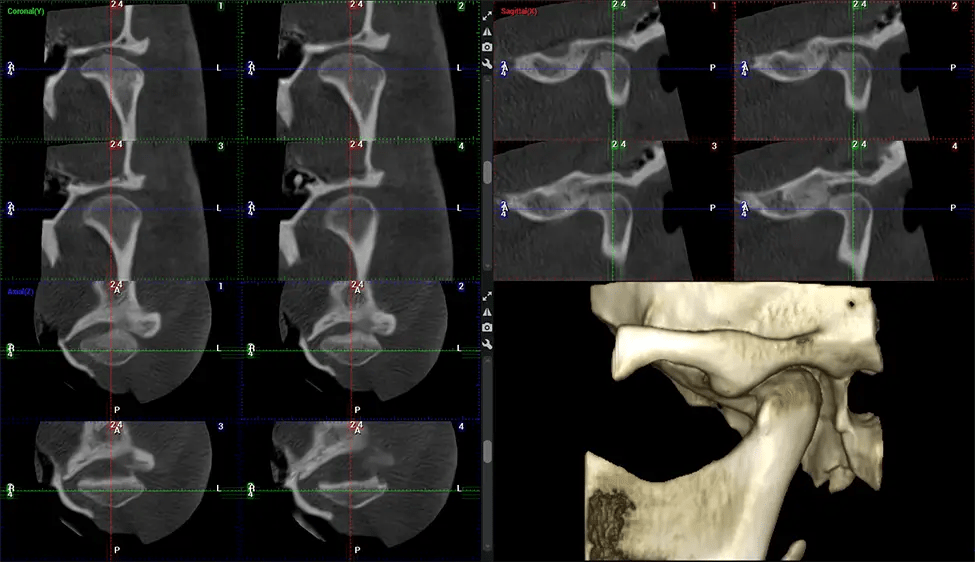

Cone Beam Computed Tomography (CBCT) is an advanced imaging technique used in dentistry and maxillofacial surgery to obtain detailed 3D images of the oral and maxillofacial structures. At Dr G Dental Studio, our CBCT scanners utilize a cone-shaped X-ray beam and a specialized detector to capture images from different angles. A computer then combines these images to create a 3D representation of the patient’s oral anatomy.

This 3D scan, called cone beam computed tomography, gives your dentist a more complete image of your oral anatomy and disease processes than a traditional X-ray. Unlike conventional X-rays, which capture a 2D image of your mouth from various angles, a 3D scan takes multiple digital X-rays for one image. It provides a complete view of your jaw, teeth, nerves, and soft tissues. This enhanced view allows dentists to detect minor issues not visible in traditional 2D scans, such as impacted wisdom teeth or bone fractures in the sinus cavity.

After the scanning process, the captured X-ray images are processed by the CBCT software, which applies algorithms to reconstruct a detailed 3D image of the scanned area. The software compiles these individual X-ray images and creates a digital 3D representation of the patient’s anatomy. The reconstructed 3D CBCT image can be viewed and analyzed by the dentist or radiologist. This image can be manipulated, rotated, and zoomed in or out to examine specific structures and evaluate the patient’s condition.

Planmeca Viso G7 CBCT ( Cone Beam CT Scan ) is designed to surpass the demands of industry leaders, specialists, and large institutions. It’s has a large ø25×30 cm sensor with four built-in cameras. It can capture unlimited volume sizes from a ø3×3 cm to a ø30x30cm volume capturing the skullcap through C7 on the cervical spine. The Planmeca Viso G7 offers the industry’s largest single volume scan of ø30×19 cm. It’s poised to handle advanced imaging modalities such as Planmeca ProFace® and Planmeca 4D™ Jaw Motion technology. The occipital head support allows an unimpeded view of facial tissue.